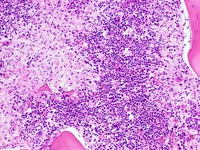

Nucleated Red Blo...